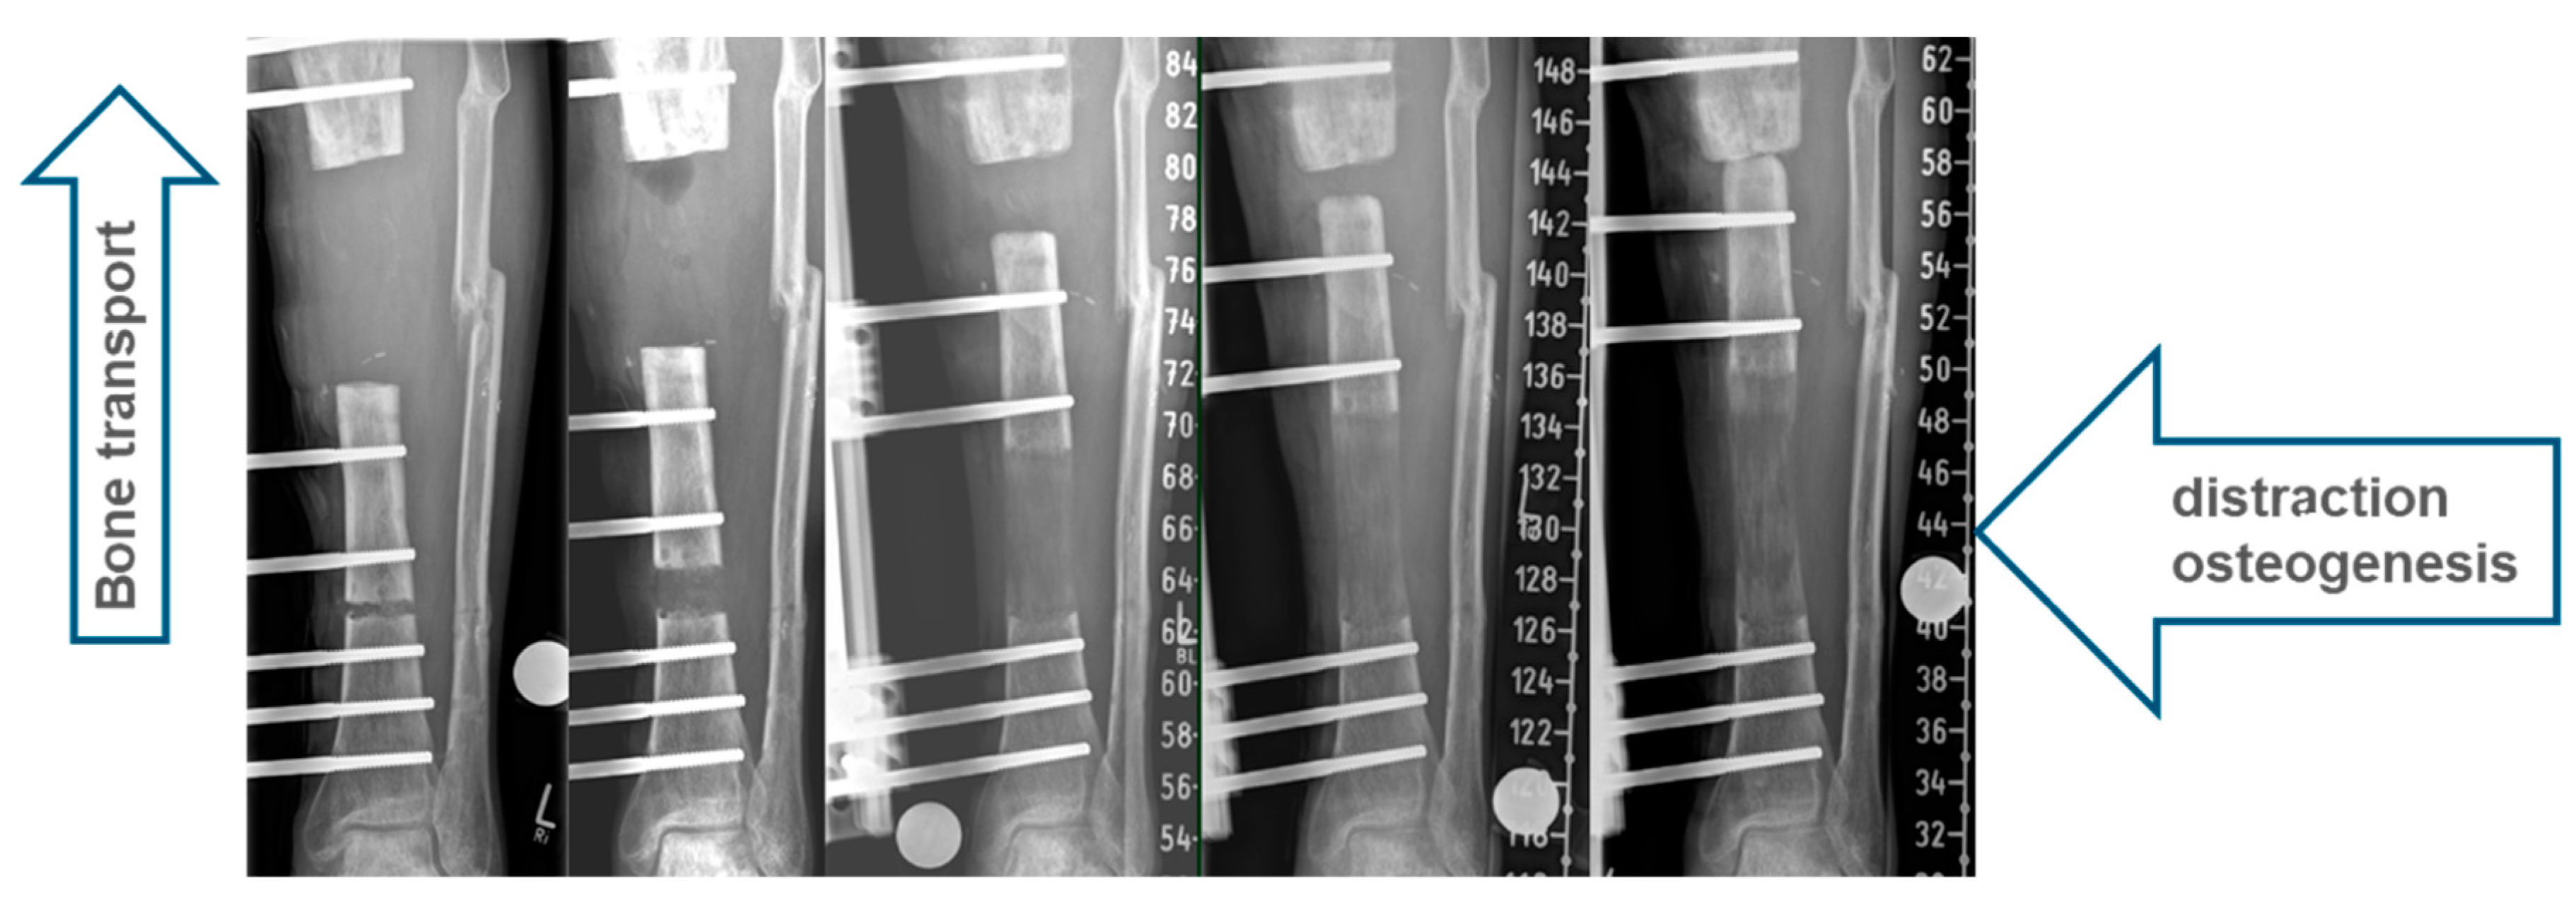

1.1. Classic Bone Transport

1.2. Hybrid Techniques of Segmental Bone Transport